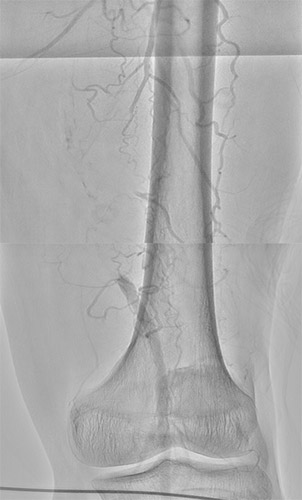

主訴は跛行(Rutherford分類3)の方で ABI検査を実施したところ0.62と低値。リスクファクターとして糖尿病(DM)、高血圧(HT)、脂質異常症(DL)が認められた。今回の標的病変は左大腿動脈(Lt. SFA CTO)【図1・図2】であり、アプローチ部位はTAI(Trans ankle intervention)にて施行することとした。

BKについてはATAは開存しており、PTAが途中から閉塞していることを確認した。【図3】